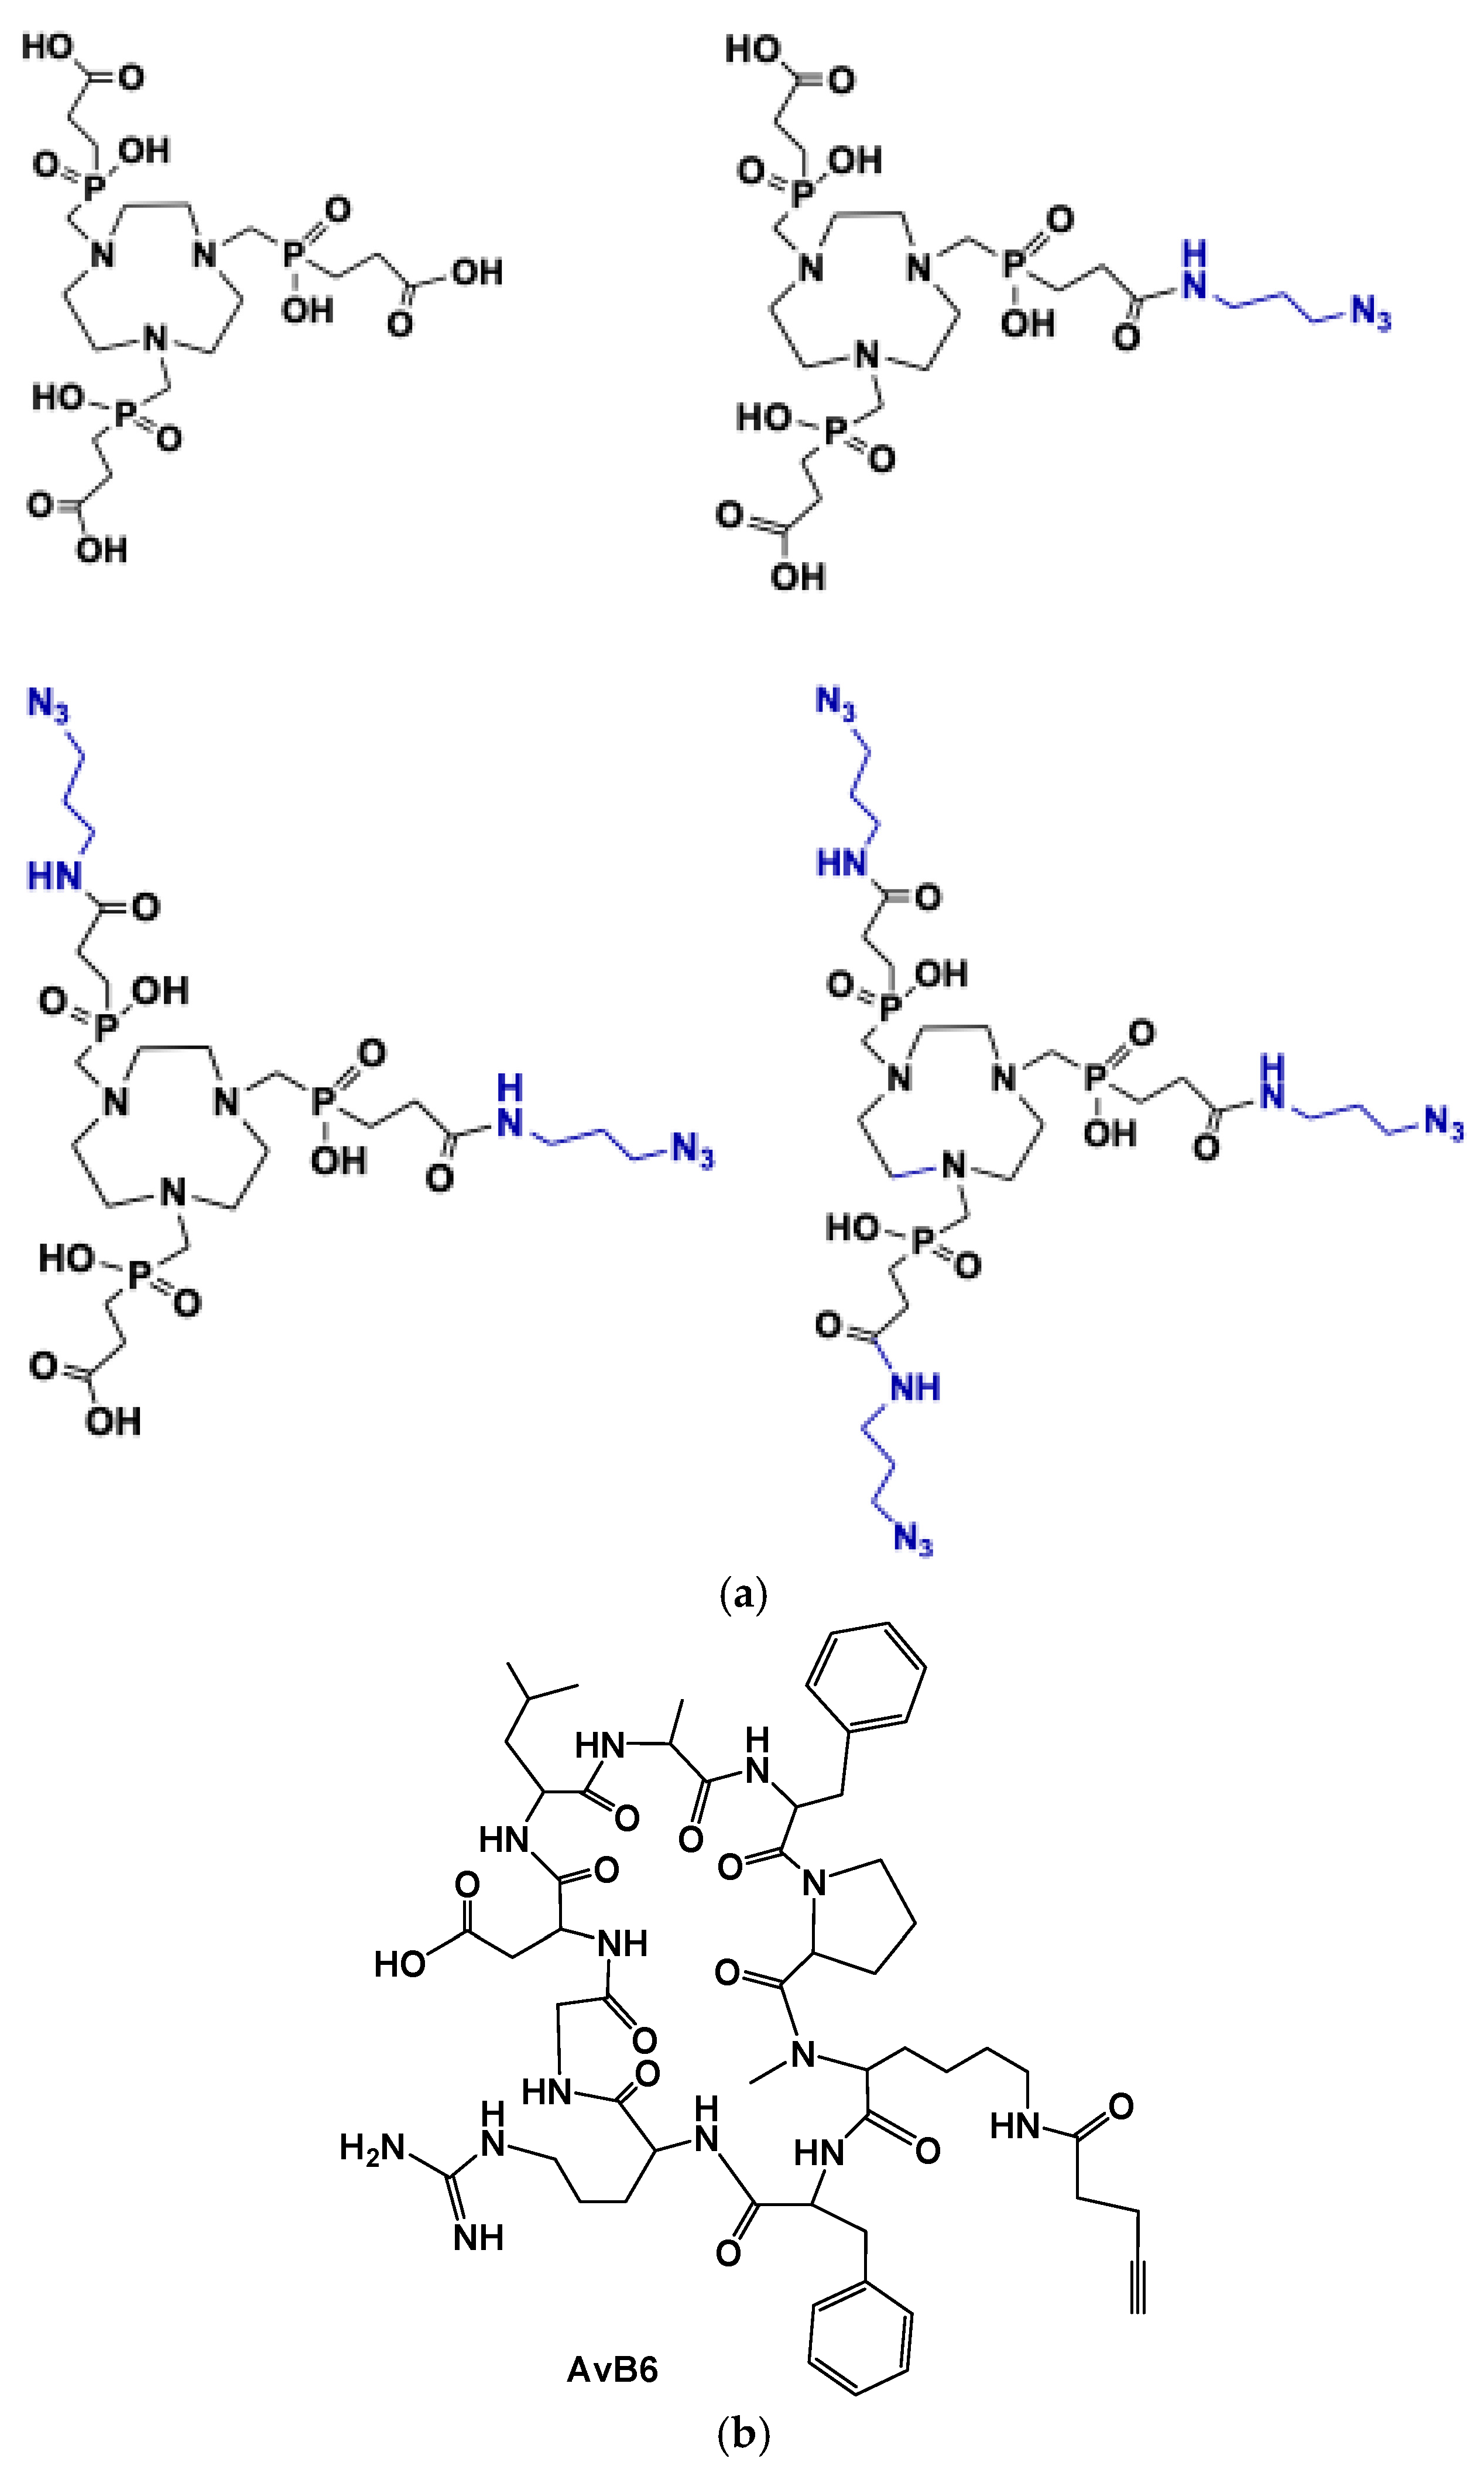

2. [68Ga]Ga-Trivehexin: A Radiochemical Insight